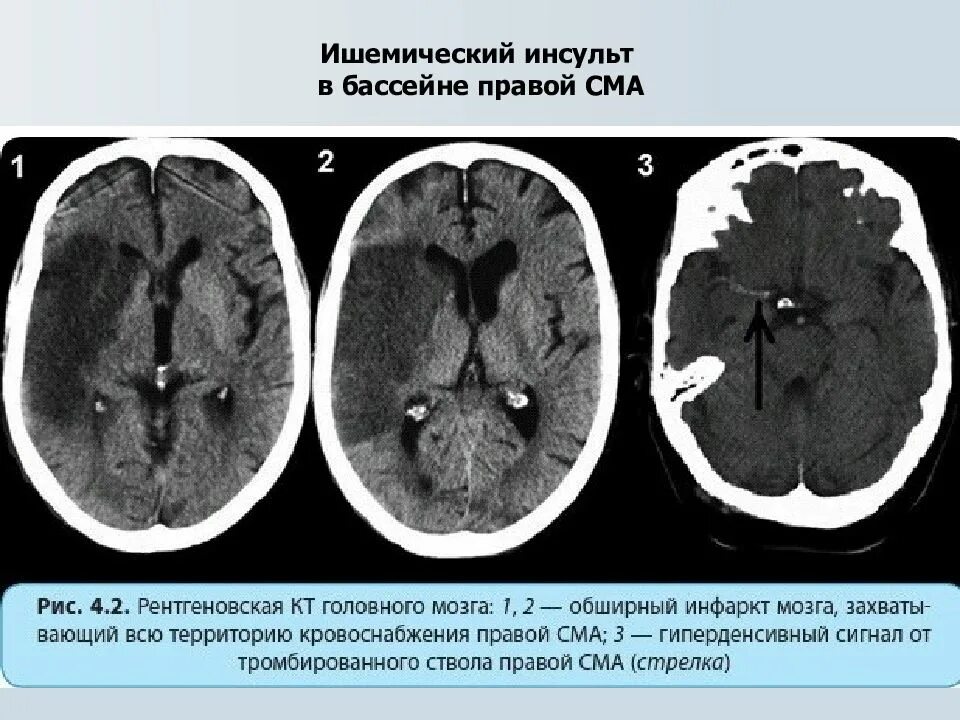

Онмк в бассейне сма